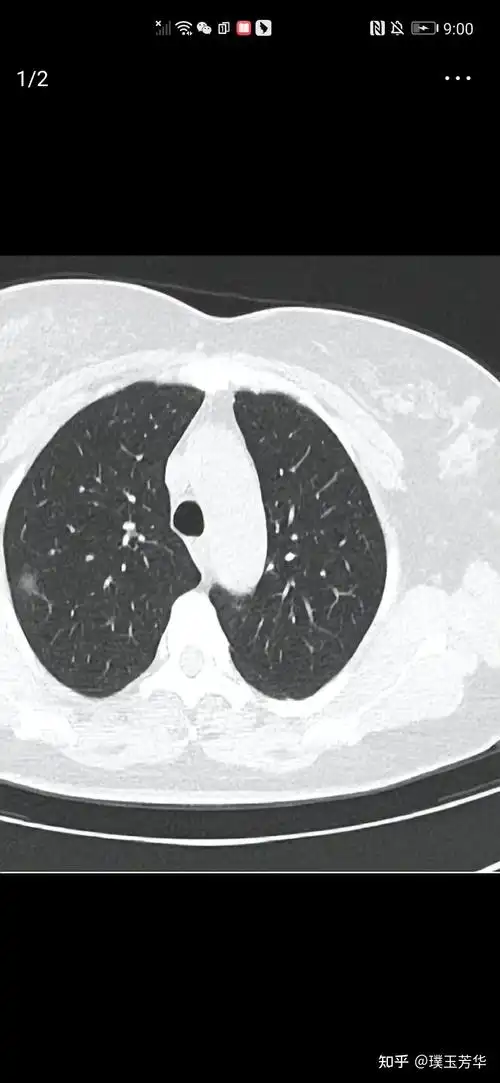

肺结节

右肺结节

56岁女性,发现左下肺结节1周.